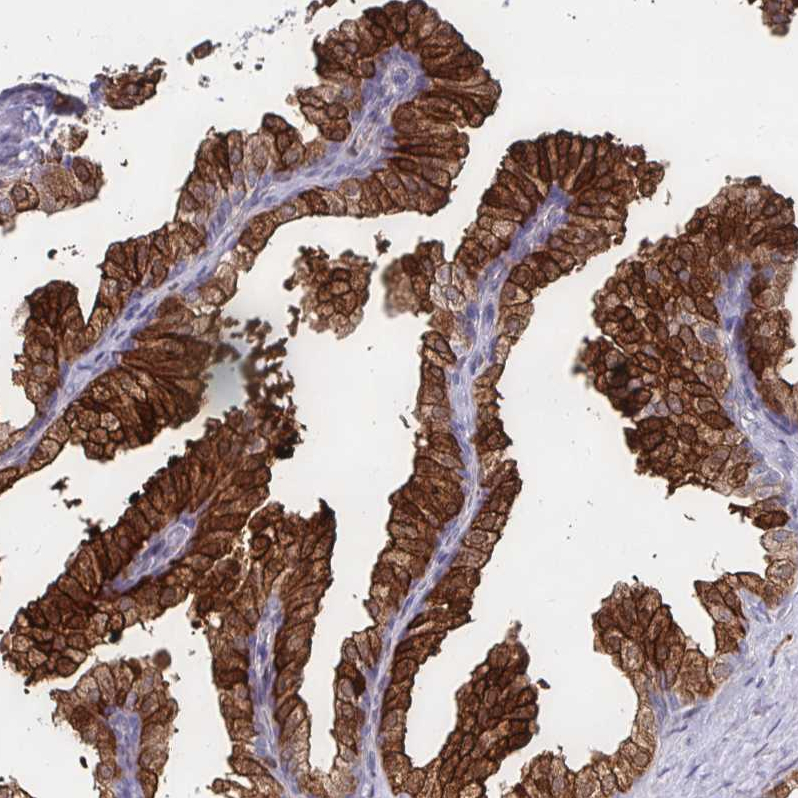

Immunohistochemical staining of human prostate shows strong cytoplasmic-membranous positivity in glandular cells.